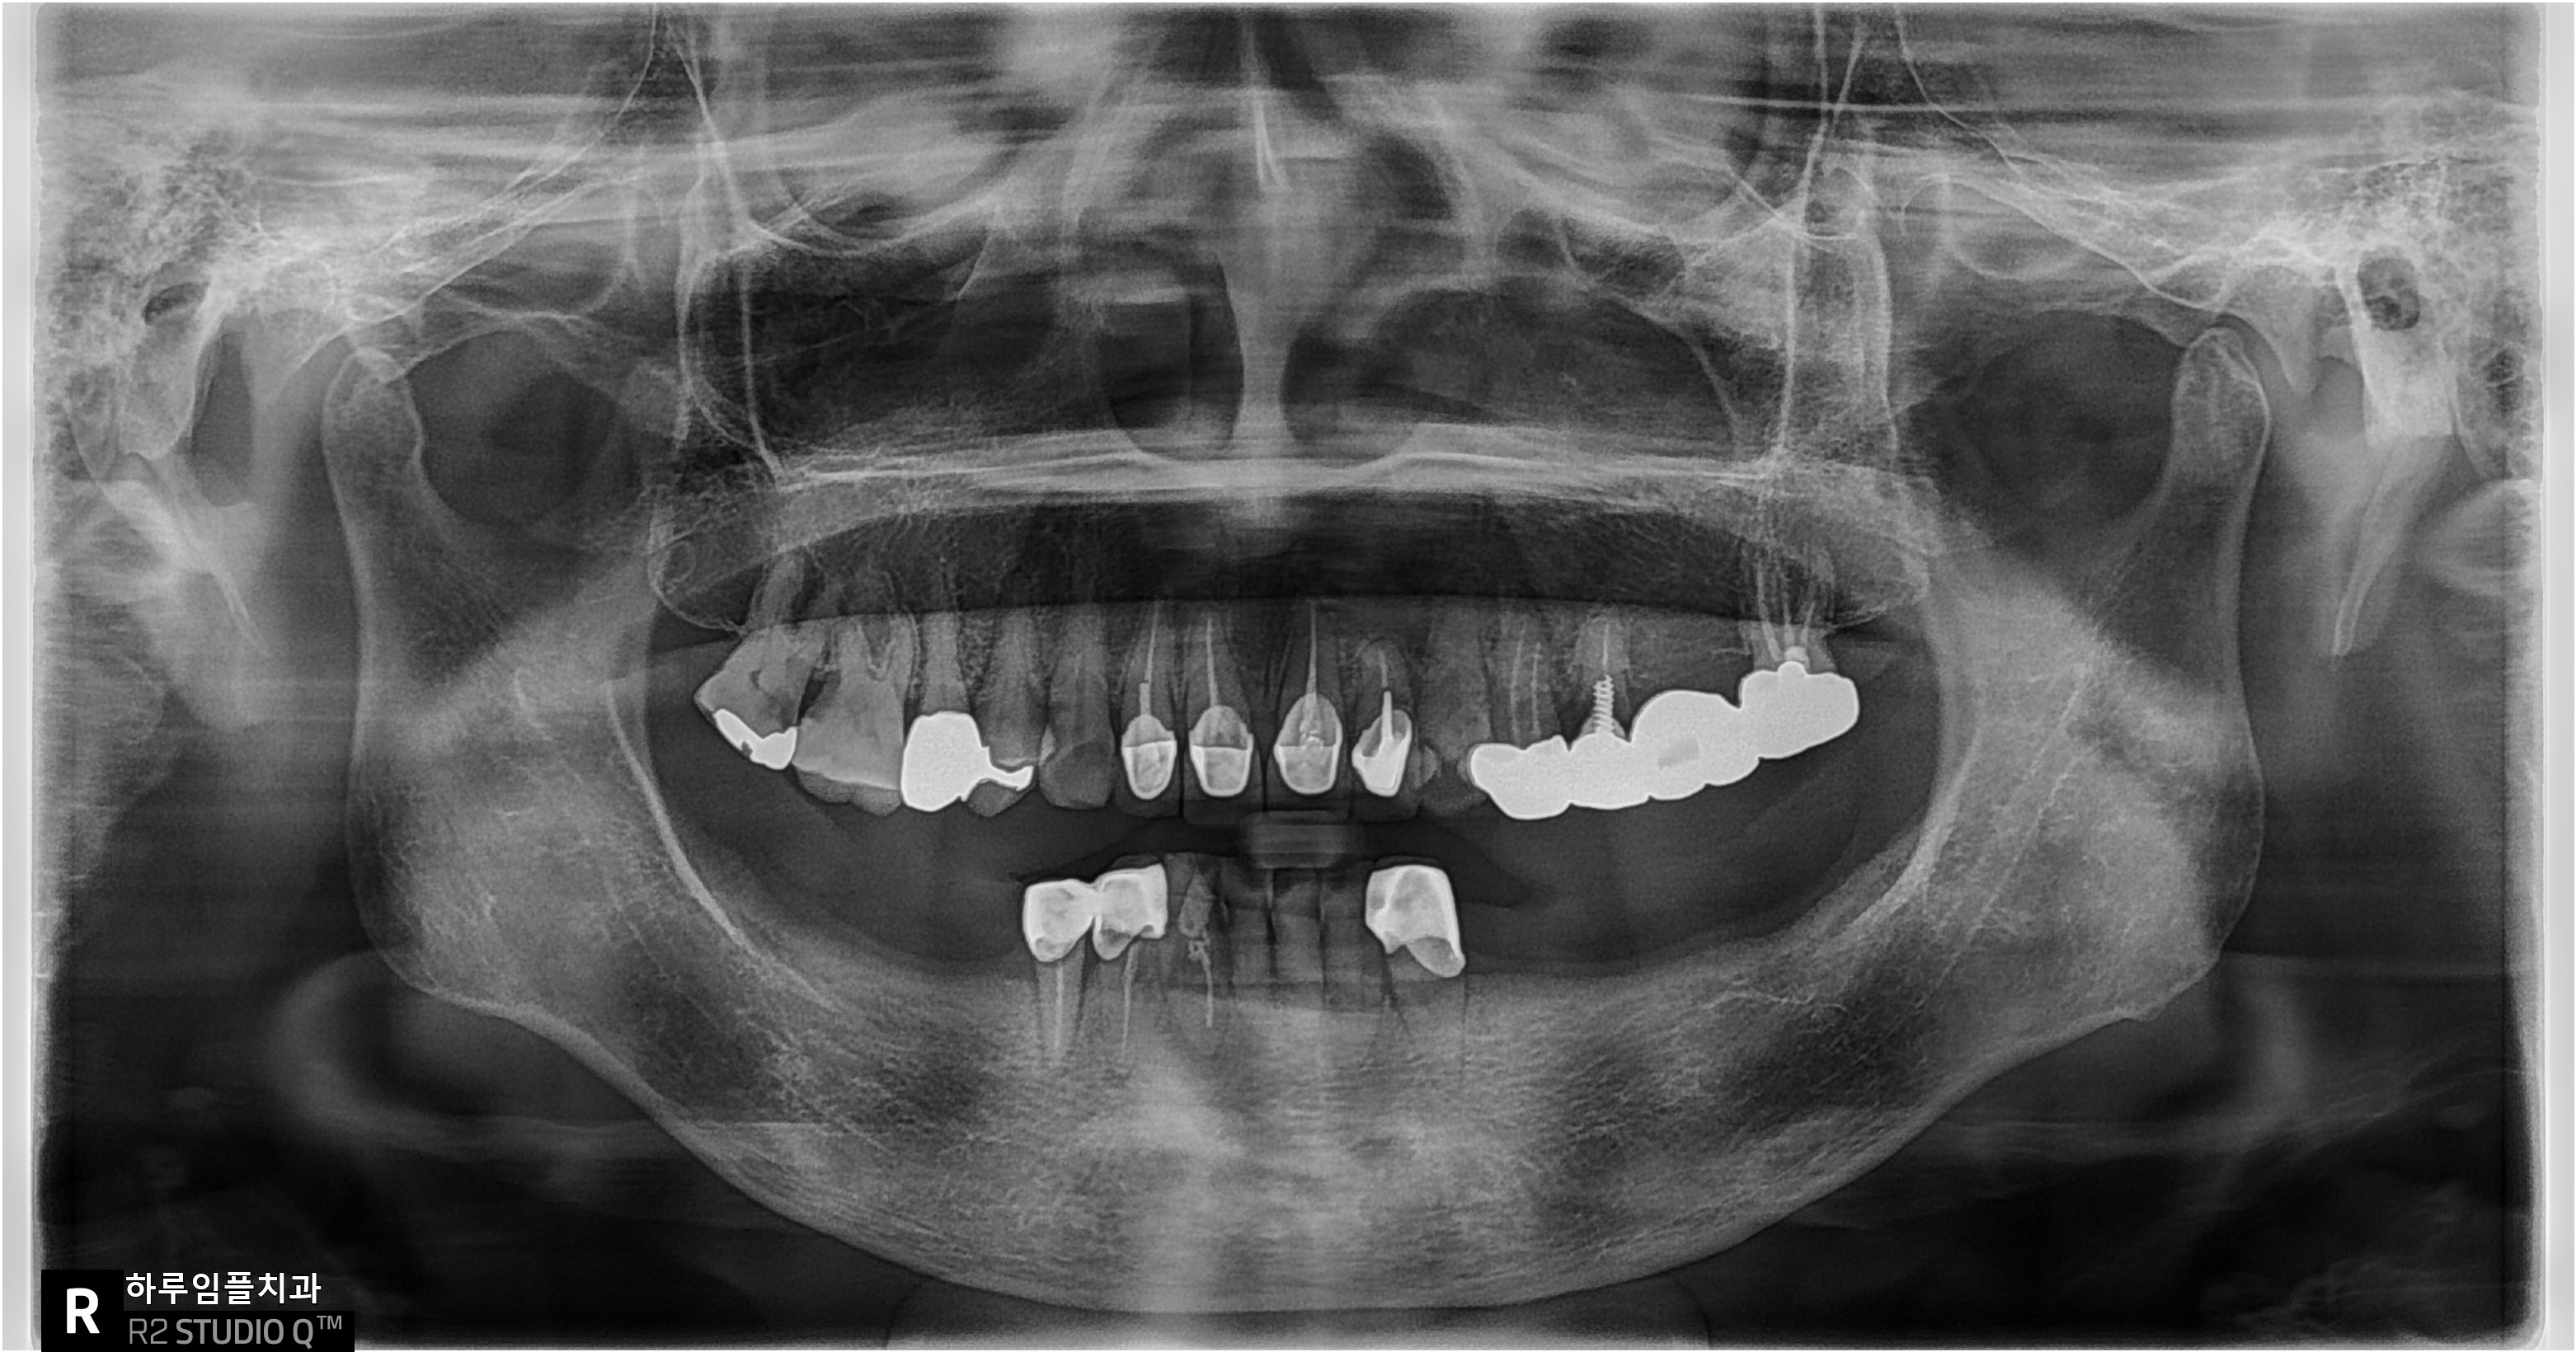

엑스레이 사진상에서도

치조골이 상당 부분 소실된 것

확인되었습니다.

환자분의 엑스레이를 보면

‘칼릿지(Crest)’라고 불리는

잇몸뼈 부분이 거의 사라져 있었습니다.

CT를 분석해보면

정말 “뼈가 없다”라고 표현할 만큼

어려운 상황이었습니다.